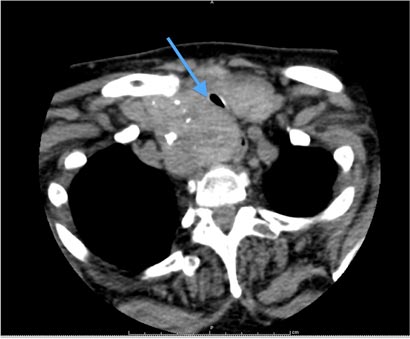

Clinical examination revealed an obvious stridor and a diffuse, symmetrically large goitre. Pemberton sign was positive. Thyroid function tests had demonstrated a suppressed thyroid-stimulating hormone level (0.03 mU/L; reference interval [RI], 0.5–4.0 mU/L), with a free thyroxine level within the RI (16.3 pmol/L; RI, 10.0–19.0 pmol/L). Ultrasound and computed tomography imaging identified a large, retrosternal, multinodular goitre. Her trachea was significantly compressed, with a diameter of 5.5 mm (Box). We further recommended total thyroidectomy, which she again politely declined.